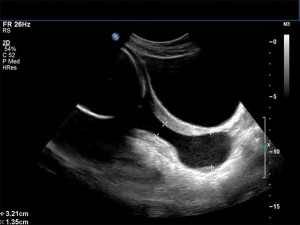

УЗИ шейки матки при наличии эрозии может выполняться двумя методами: через введение ультразвукового датчика во влагалище или при исследовании нижней части живота (что подходит для девственниц и беременных женщин). При внутреннем введении датчика эрозия становится более четкой и заметной. Врач наблюдает ее на специальном экране, где пораженные участки выделяются другим цветом.

С помощью данного диагностического метода можно оценить состояние слизистой оболочки, ее клеточный состав, толщину и размеры. Кроме того, ультразвуковой датчик позволяет выявить изменения в кровоснабжении. Обычно пораженные ткани имеют менее выраженное кровоснабжение. Более подробно о том, как проходит УЗИ шейки матки, можно узнать на изображении ниже.